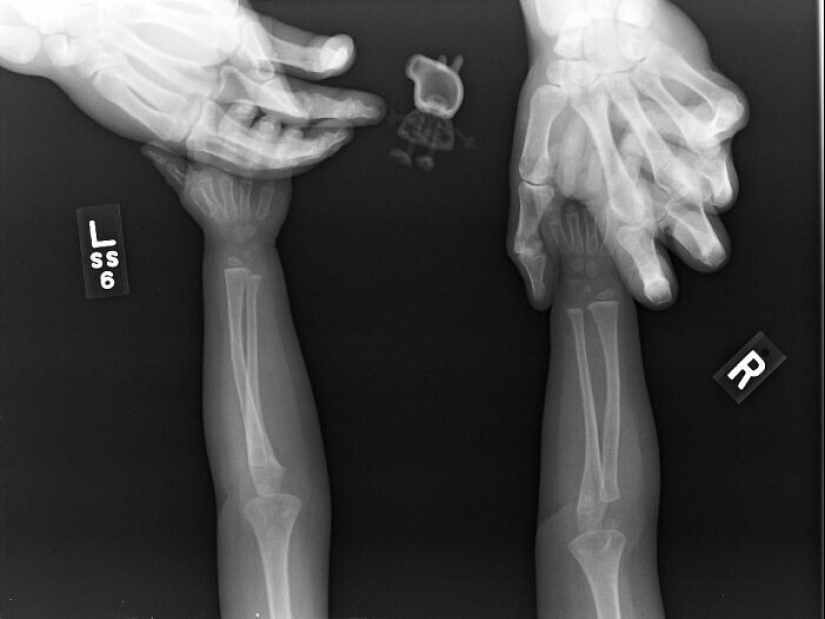

"A mi hija le preguntó a Peppa pig pasó por los rayos x junto con ella"